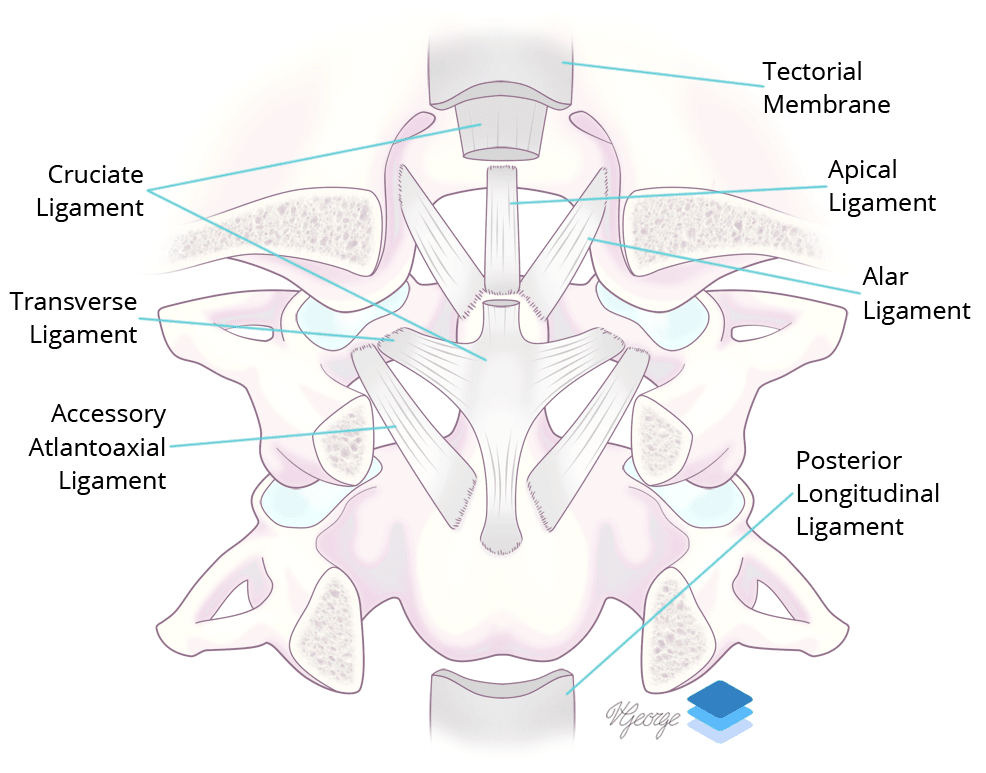

- Remember that the alar ligaments attach to the occipital condyle. Displaced avulsion fractures are considered unstable injuries concerning for underlying ligament injury, and while you do not need to know the surgical classification schemes, make sure to mention whether or not these fractures are displaced

Coronal view of the major ligaments at the craniocervical junction.